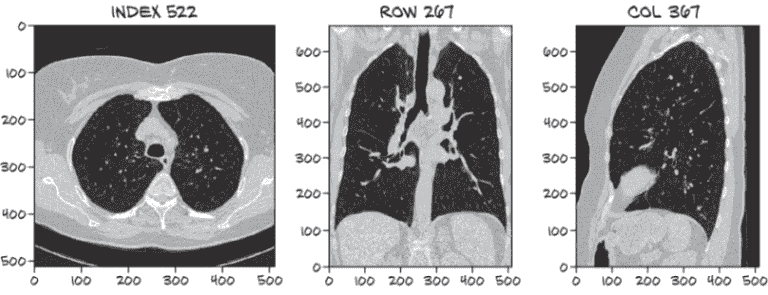

你能够在图 9.5 的三个视图中识别被标记为结节的白点吗?²

如果你需要提示,索引、行和列值可以帮助找到相关的密集组织块。你认为只有这些图像(这意味着只有图像–没有索引、行和列信息!)你能找出肿瘤的相关特性吗?如果你被给予整个 3D 扫描,而不仅仅是与扫描的有趣部分相交的三个切片呢?

注意 如果你找不到肿瘤,不要担心!我们试图说明这些数据有多微妙–难以在视觉上识别是这个例子的全部意义。

图 9.5 一张 CT 扫描,大约有 1,000 个对于未经训练的眼睛看起来像肿瘤的结构。当由人类专家审查时,只有一个被确定为结节。其余的是正常的解剖结构,如血管、病变和其他无问题的肿块。